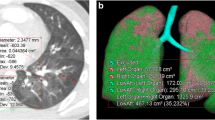

All examinations were analyzed in a commercially available workstation (Advantage Workstation 4.6, General Electric Healthcare Technologies, Waukesha, WI, USA). Inspiratory and expiratory CT images were evaluated using dedicated software designed for the assessment of segmented images from the chest wall, mediastinum, diaphragm, and airways. Automated segmentation of the transplanted lung from the chest wall and mediastinum was performed and the total lung volume and attenuation of all voxels included in the lung segmentation were quantified. The expiratory air-trapping index (ATIexp) was calculated as the percentage of lung voxels with attenuation of − 950 to − 856HU on expiratory CT images [15] (Fig. 1). Mean lung density (MLD) histograms were created for expiratory and inspiratory acquisitions for each subject, and the expiration and inspiration ratio of MLD (E/I-ratio(MLD) was calculated [22, 23]. Measurements were performed by 2 thoracic radiologists in consensus, with a minimum of 10 years of experience, blinded to all clinical information. Analysis of all measurements required approximately five minutes per patient.

Coronal (1A) and axial (1B) slices of expiratory high resolution CT scan of the chest from a single lung transplant patient with BOS. Images 2A, 2B e 2C show the 3D-CT reconstruction of the lungs and images 3A, 3B e 3C show the same 3D-CT reconstruction highlighting areas of air trapping in the transplanted lung only (red color), represented by lung voxels with attenuation of − 950 to − 856 HU